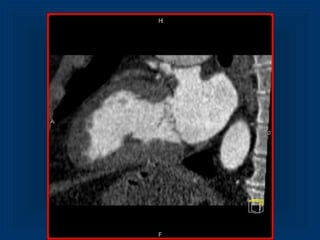

Patient without ACSPatientwithout ACS 43 year old female, 3 hours of substernal chest pain radiating to the back, negative initial Troponin and CK-MB, ECG: sinus bradycardia

• 25.